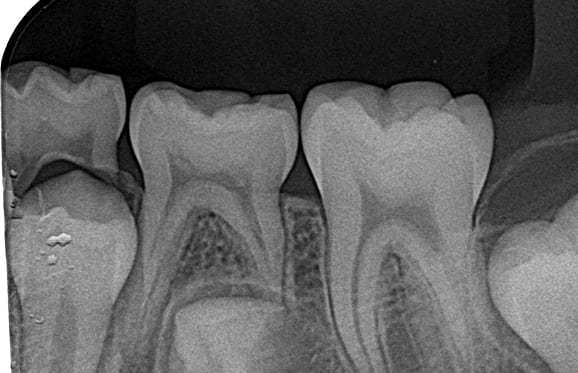

01 左下7の近心根にエンジンファイルの破折

02 ファイル除去時

※根尖周囲の透過像はまだ残存

03 最終の根充剤を充填

※根尖透過像が小さく治癒方向へ向かっている